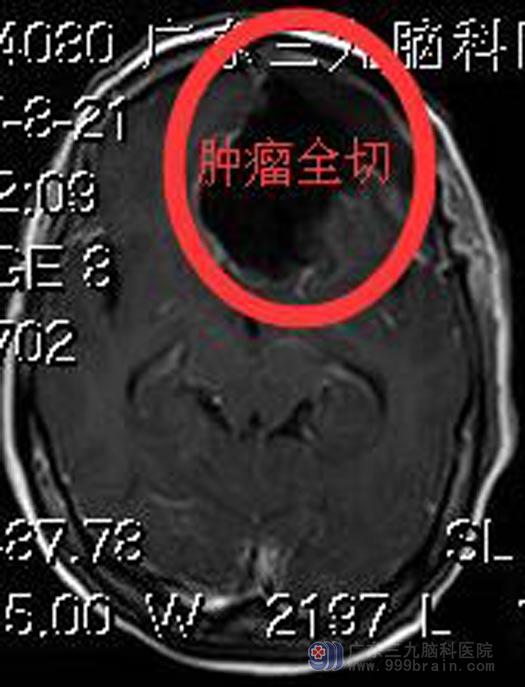

鲁明主任主刀,在全麻下行前颅底脑膜瘤切除术,术中显微镜下见肿瘤呈灰白色,质中,边界清楚,视神经受压明显,术中连同受侵犯大脑镰一并完整切除,手术过程顺利。术后谢阿姨神志清醒,视物正常。现已康复出院,病理回报:脑膜瘤,合体细胞型,WHO I级。